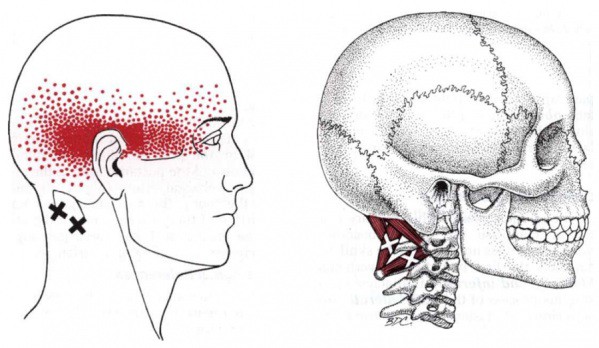

Obr. 4: TrP v m.rectus capitis posterior major (jeden z krátkých extenzorů šíje

(zdroj: http://www.physio-pedia.com/Rectus_Capitis_Posterior_Major)

Obr. 5: TrPs v m.sternocleidomastodeus a jejich projekce bolesti

(zdroj: http://fortefitness.com/trigger-point-for-tension-headaches-stiff-necks-tmj)

Cervikogenní bolesti hlavy jsou doprovázeny změnou tonu šíjového svalstva. Významnou roli mají především krátké suboccipitální svaly (krátké extenzory šíje) a jejich přetěžování právě v důsledku předsunutého držení hlavy. Dále jsou přítomny bolestivé spoušťové body v m.sternocleidomastoideus, mm.scaleni, ale také v m.trapezius či m.levator scapulae. Při tlaku na TrP v uvedených svalech bolest vyzařuje do do týla, oblasti spánků nebo temene, někdy až do čelní krajiny či retrobulbárně (za oči).